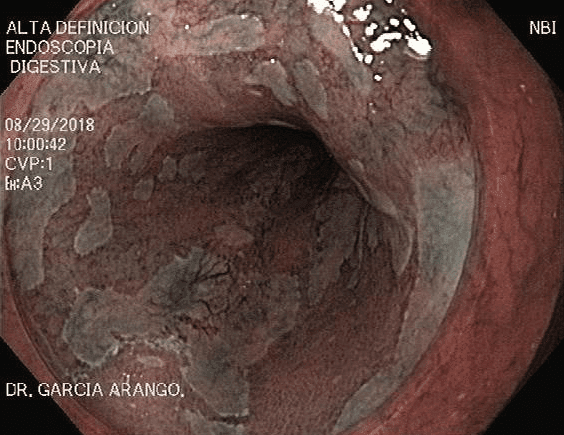

ENDOSCOPIA DIAGNÓSTICA Y TERAPÉUTICA AVANZADA CON ALTA DEFINICIÓN

⚕ Endoscopia de alta definición

⚕ Detección de cáncer de tubo digestivo

⚕ Videoendoscopia y biopsias